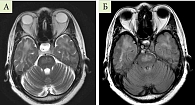

Рис. 1. МРТ головного мозга пациентки А. 35 лет, от 16.03.2021 г. в Т2, Т2-FLAIR ВИ: А – до введения контраста; Б – после введения контраста

На магнитно-резонансной томограмме (МРТ) головного мозга (ГМ) пациентки с контрастным усилением от 16.03.2021 г.: обнаружены признаки диффузного объемного поражения моста (умеренное объемное увеличение моста, плотность его неоднородно повышена в Т2-, Т2-FLAIR-взвешенных изображениях (ВИ), после введения контраста выявляется его незначительное неравномерное накопление в мосту) (рис. 1).

На фоне ГКС-терапии и коррекции нутритивного статуса отмечалась выраженная положительная неврологическая динамка: исчезновение нистагма, увеличение звучности голоса, увеличение мышечной силы конечностей. На МРТ ГМ от 26.03.2021 г.: уменьшение зоны перифокального отека и распространенности, контрастирование по периферии − менее четкое, местами менее интенсивное. Рекомендации к дальнейшему лечению включали продолжение приема ГКС, проведение повторной колоноскопии и МРТ ГМ с контрастированием через месяц. Выписана в удовлетворительном состоянии.

Заключение МРТ ГМ с внутривенным контрастированием от 10.02.2022 г.: при сравнении с исследованием от 16.03.2021 г. отмечается выраженная положительная динамика в виде уменьшения моста в размерах, отсутствия перифокальной реакции, замещения зоны патологической перестройки кистозным рубцом и отсутствием ее контрастирования, что позволяет включить в дифференциально-диагностический ряд демиелинизирующий процесс, нарушение мозгового кровообращения в бассейне вертебро-базиллярных артерий в анамнезе.